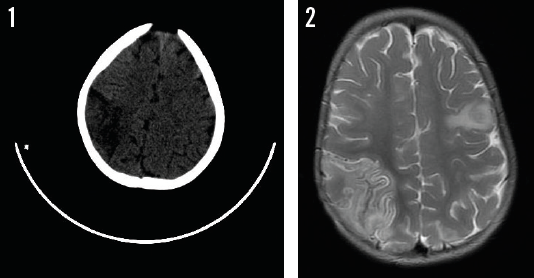

Kimberley Monks, BS; Erica H.Z. Wang, PharmD; Margaret Trost, MD

A 1-month-old boy presented with a 1-day history of fussiness, decreased feeding, and fever.

08/27/2015